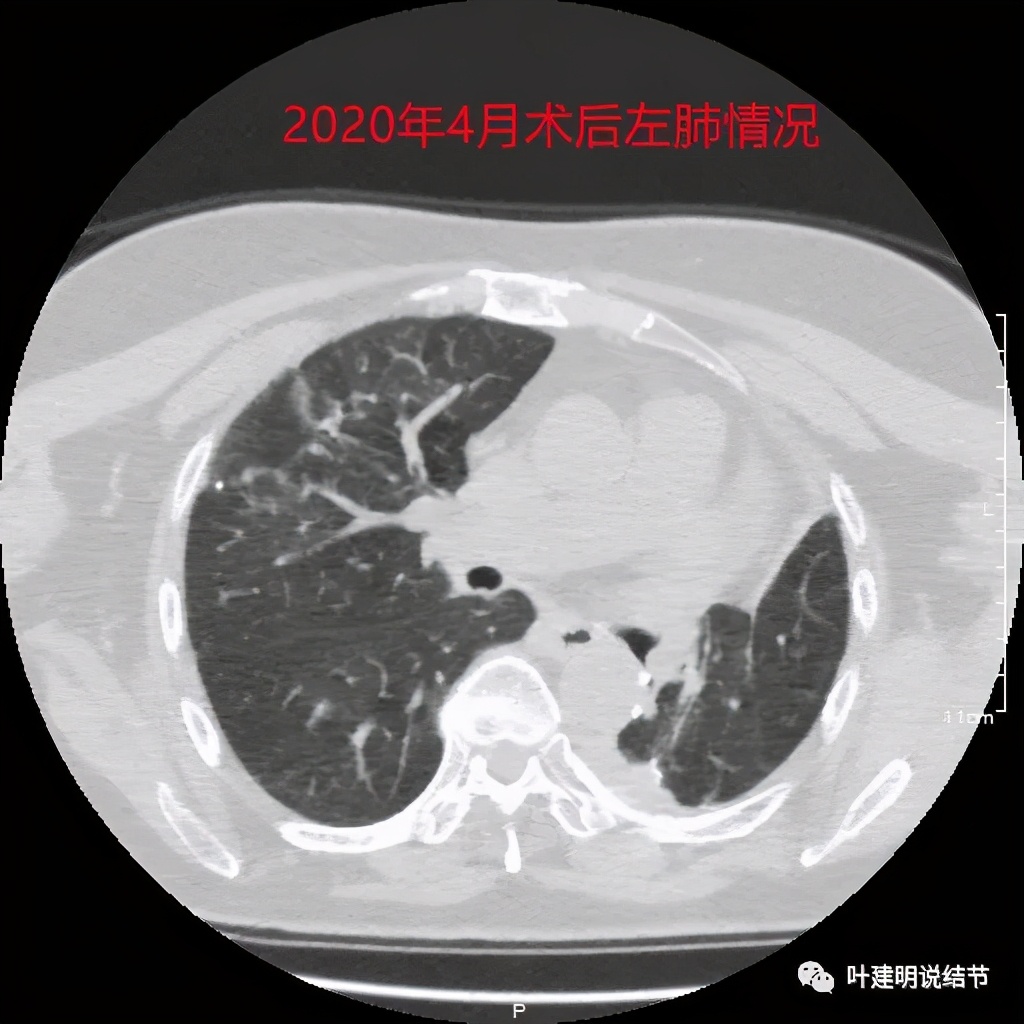

上图是当时的病理报告。上叶是支气管囊肿伴上皮鳞状化生,伴囊内真菌感染;左下叶是浸润性腺癌,乳头型为主,部分腺泡型,淋巴结是阴性的。但她的肺确实是影响大,下面是术后左肺的样子:

就留这么点肺,还是膨胀开了,虽然恢复慢,最后终于逐渐好转了一些: